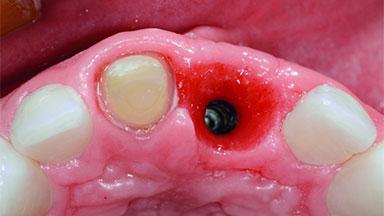

Replacement of an Ankylosed Upper Left Central Incisor: Bone Augmentation and Socket Grafting, Late Placement of an RC Bone Level Implant

# of Implants 1

Type of Implants Two-Piece

Bone Augmentation Horizontal|Simultaneous|Staged

Augmentation Materials Autogenous chips|Xenogenous

Bone Volume Deficient horizontally, requiring prior grafting